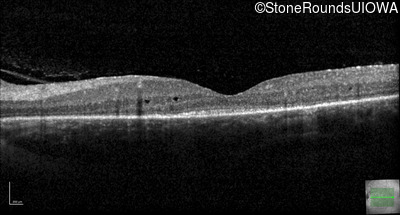

Optical Coherence Tomography - Left - 20/50 -3

Exemplar / OCT Stack